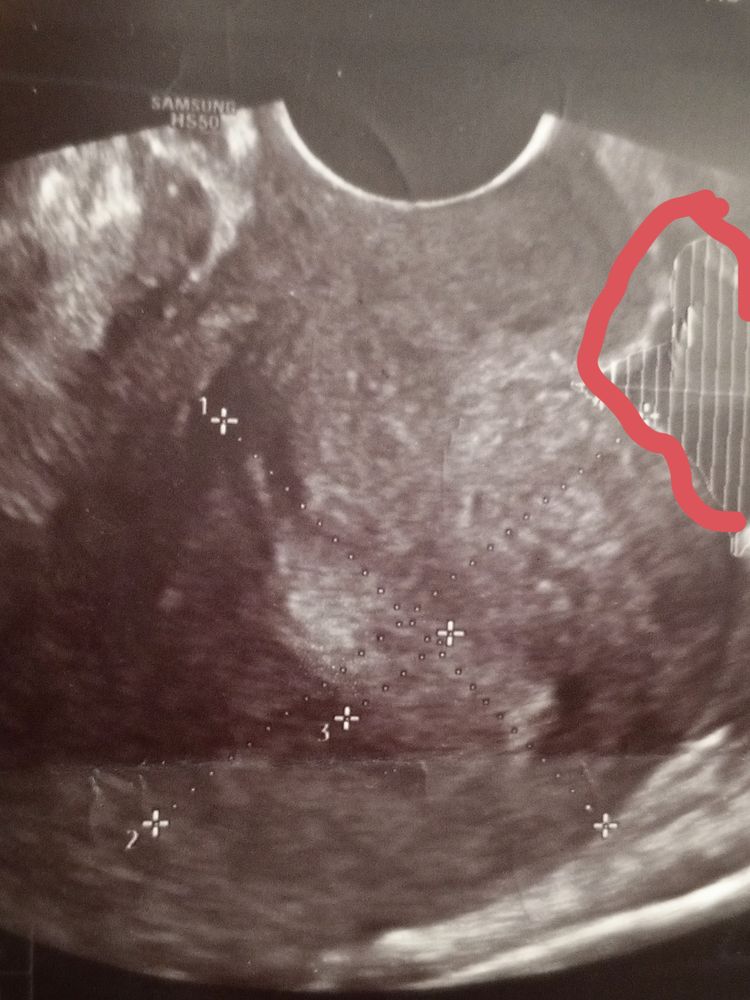

Светлана , вот смотрите первая и вторая фаза, мне кажется у вас не было овуляции и эндометрий на 1 фазу, т.к. видно линию смыкания, но я не узист конечно, просто уже за кучу узи у себя различаю Изображение Изображение

Аня, вот это как я понимаю эндометрий или нет? Изображение

Светлана , вот у вас эндометрий, слева это ближе ко дну матки, а справа к шейке Изображение